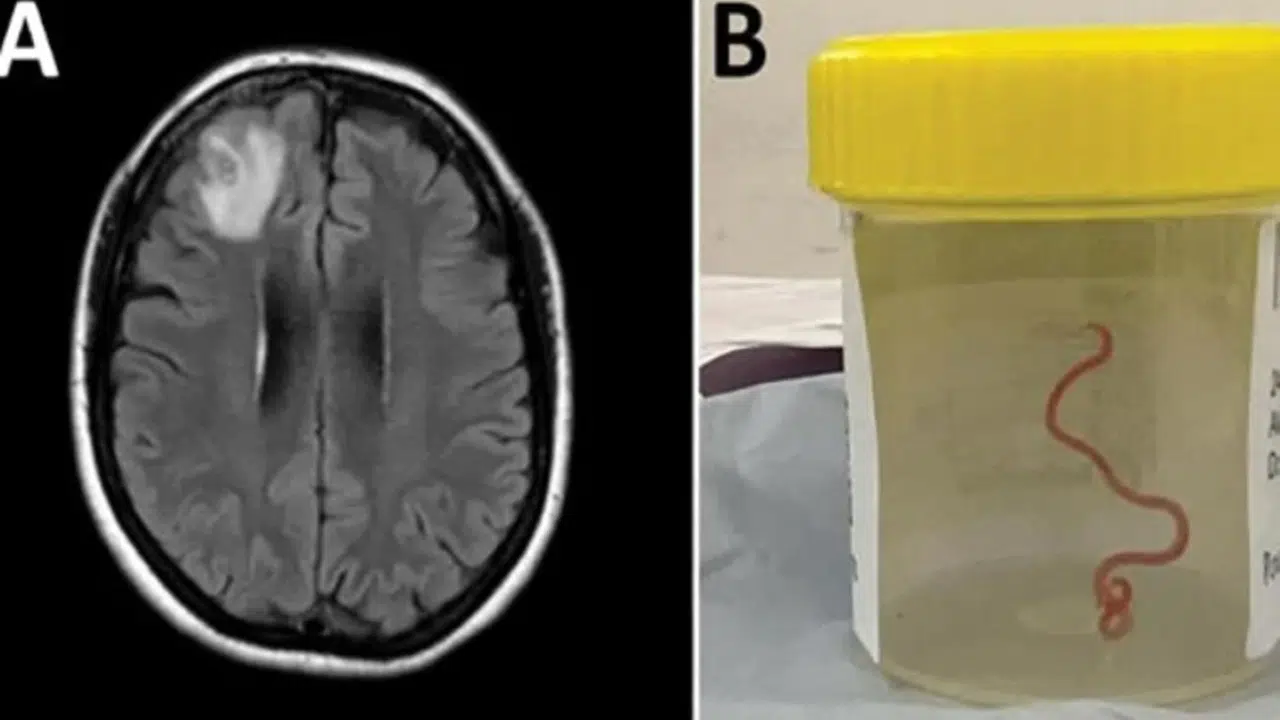

Avustralya Ulusal Üniversitesi’nden (ANU) yapılan açıklamaya göre 64 yaşındaki bir kadın karın ağrısı, ishal, kuru öksürük, ateş ve geceleri terleme şikayetleriyle ilk olarak Ocak 2021'in sonlarında hastaneye kaldırıldı. Daha sonra 2022 yılında unutkanlık ve depresyon şikayetleri de görülen kadın, Canberra Hastanesi'ne sevk edildi. MR taraması yapılan kadının, beyninin sağ ön lobunda anormallik tespit edilmesi üzerine ameliyat kararı verildi. Ameliyat sırasında doktorlar, kadının beyninde 8 santimetre uzunluğunda canlı solucan buldu. Latince adı "Ophidascaris robertsi" olan solucanın normalde piton yılanlarında bulunan bir parazit olduğu belirtildi. ANU ve Canberra Hastanesi'nin önde gelen bulaşıcı hastalık uzmanı Doçent Sanjaya Senanayake, “Bu, dünyada bir insanda görülen ile Ophidascaris vakasıdır” ifadesini kullandı.